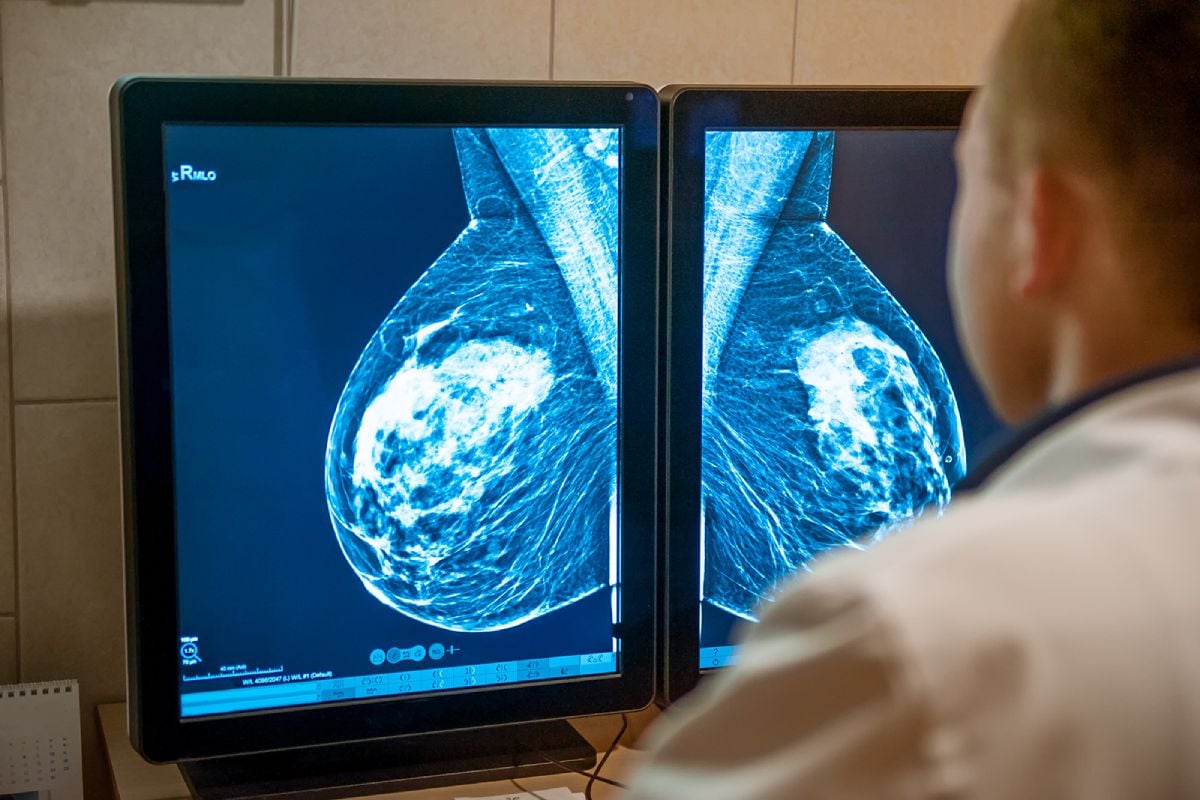

Kombinationen av tidig upptäckt och effektiva återfallsförebyggande behandlingar har resulterat i att prognosen för bröstcancer är god. Ju tidigare en tumör upptäcks desto större är chansen att bli helt frisk. Det är därför viktigt att gå på de mammografiundersökningar man blir kallad till. Alla regioner erbjuder regelbundna kontroller med mammografi för kvinnor mellan 40 och 74 år. Alla bröstcancertumörer syns inte på mammografi och därför ska alltid sjukvården kontaktas om man får symtom som kan tyda på bröstcancer, även om man nyligen varit på mammografi.